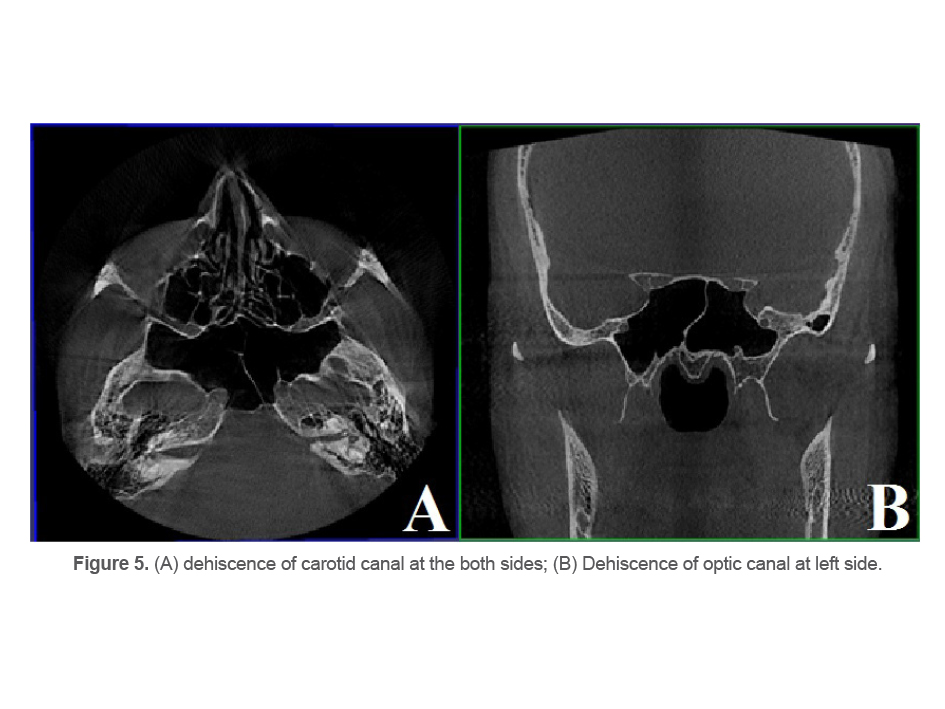

Dehiscence of optic and carotid canals

In the coronal plane, dehiscence of optic canal was detected as fading of part of the opaque rim around the optic nerve (Figure 5).

In the axial plane, dehiscence of carotid canal was detected as fading of part of the opaque rim around the internal carotid artery (Figure 5).

Optic canal and carotid canal dehiscence were recorded in 48.3% (n=145) and 40.3% (n=121) of the patients, respectively.

In the present study, optic canal dehiscence had a prevalence of 48.3%. This rate was 40.6% in the study by Hewaidi et al (25) and 64.2% in the study by Movahedian et al (4).

Dehiscence of carotid canal was reported in 40.3% of the patients in the present study, which was exactly the same as the rate reported by Hewaidi et al (25). This value was 42.8% in the study by Movahedian et al (4).

Figure 5. (A) dehiscence of carotid canal at the both sides; (B) Dehiscence of optic canal at left side.